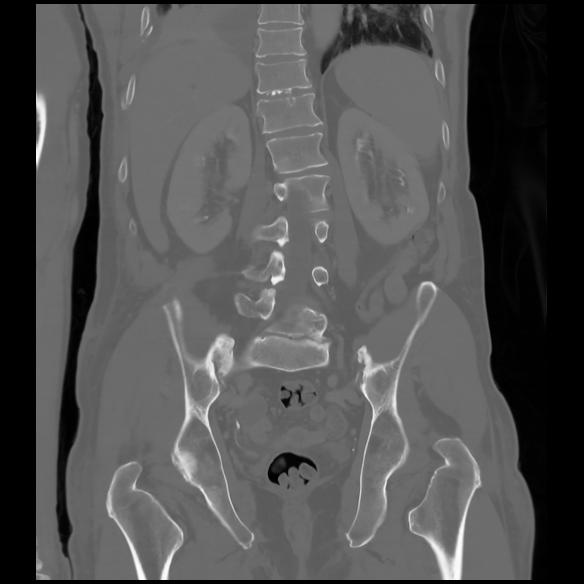

6 CUERPO,CE,Coronal,3.000,CUERPO,Coronal,